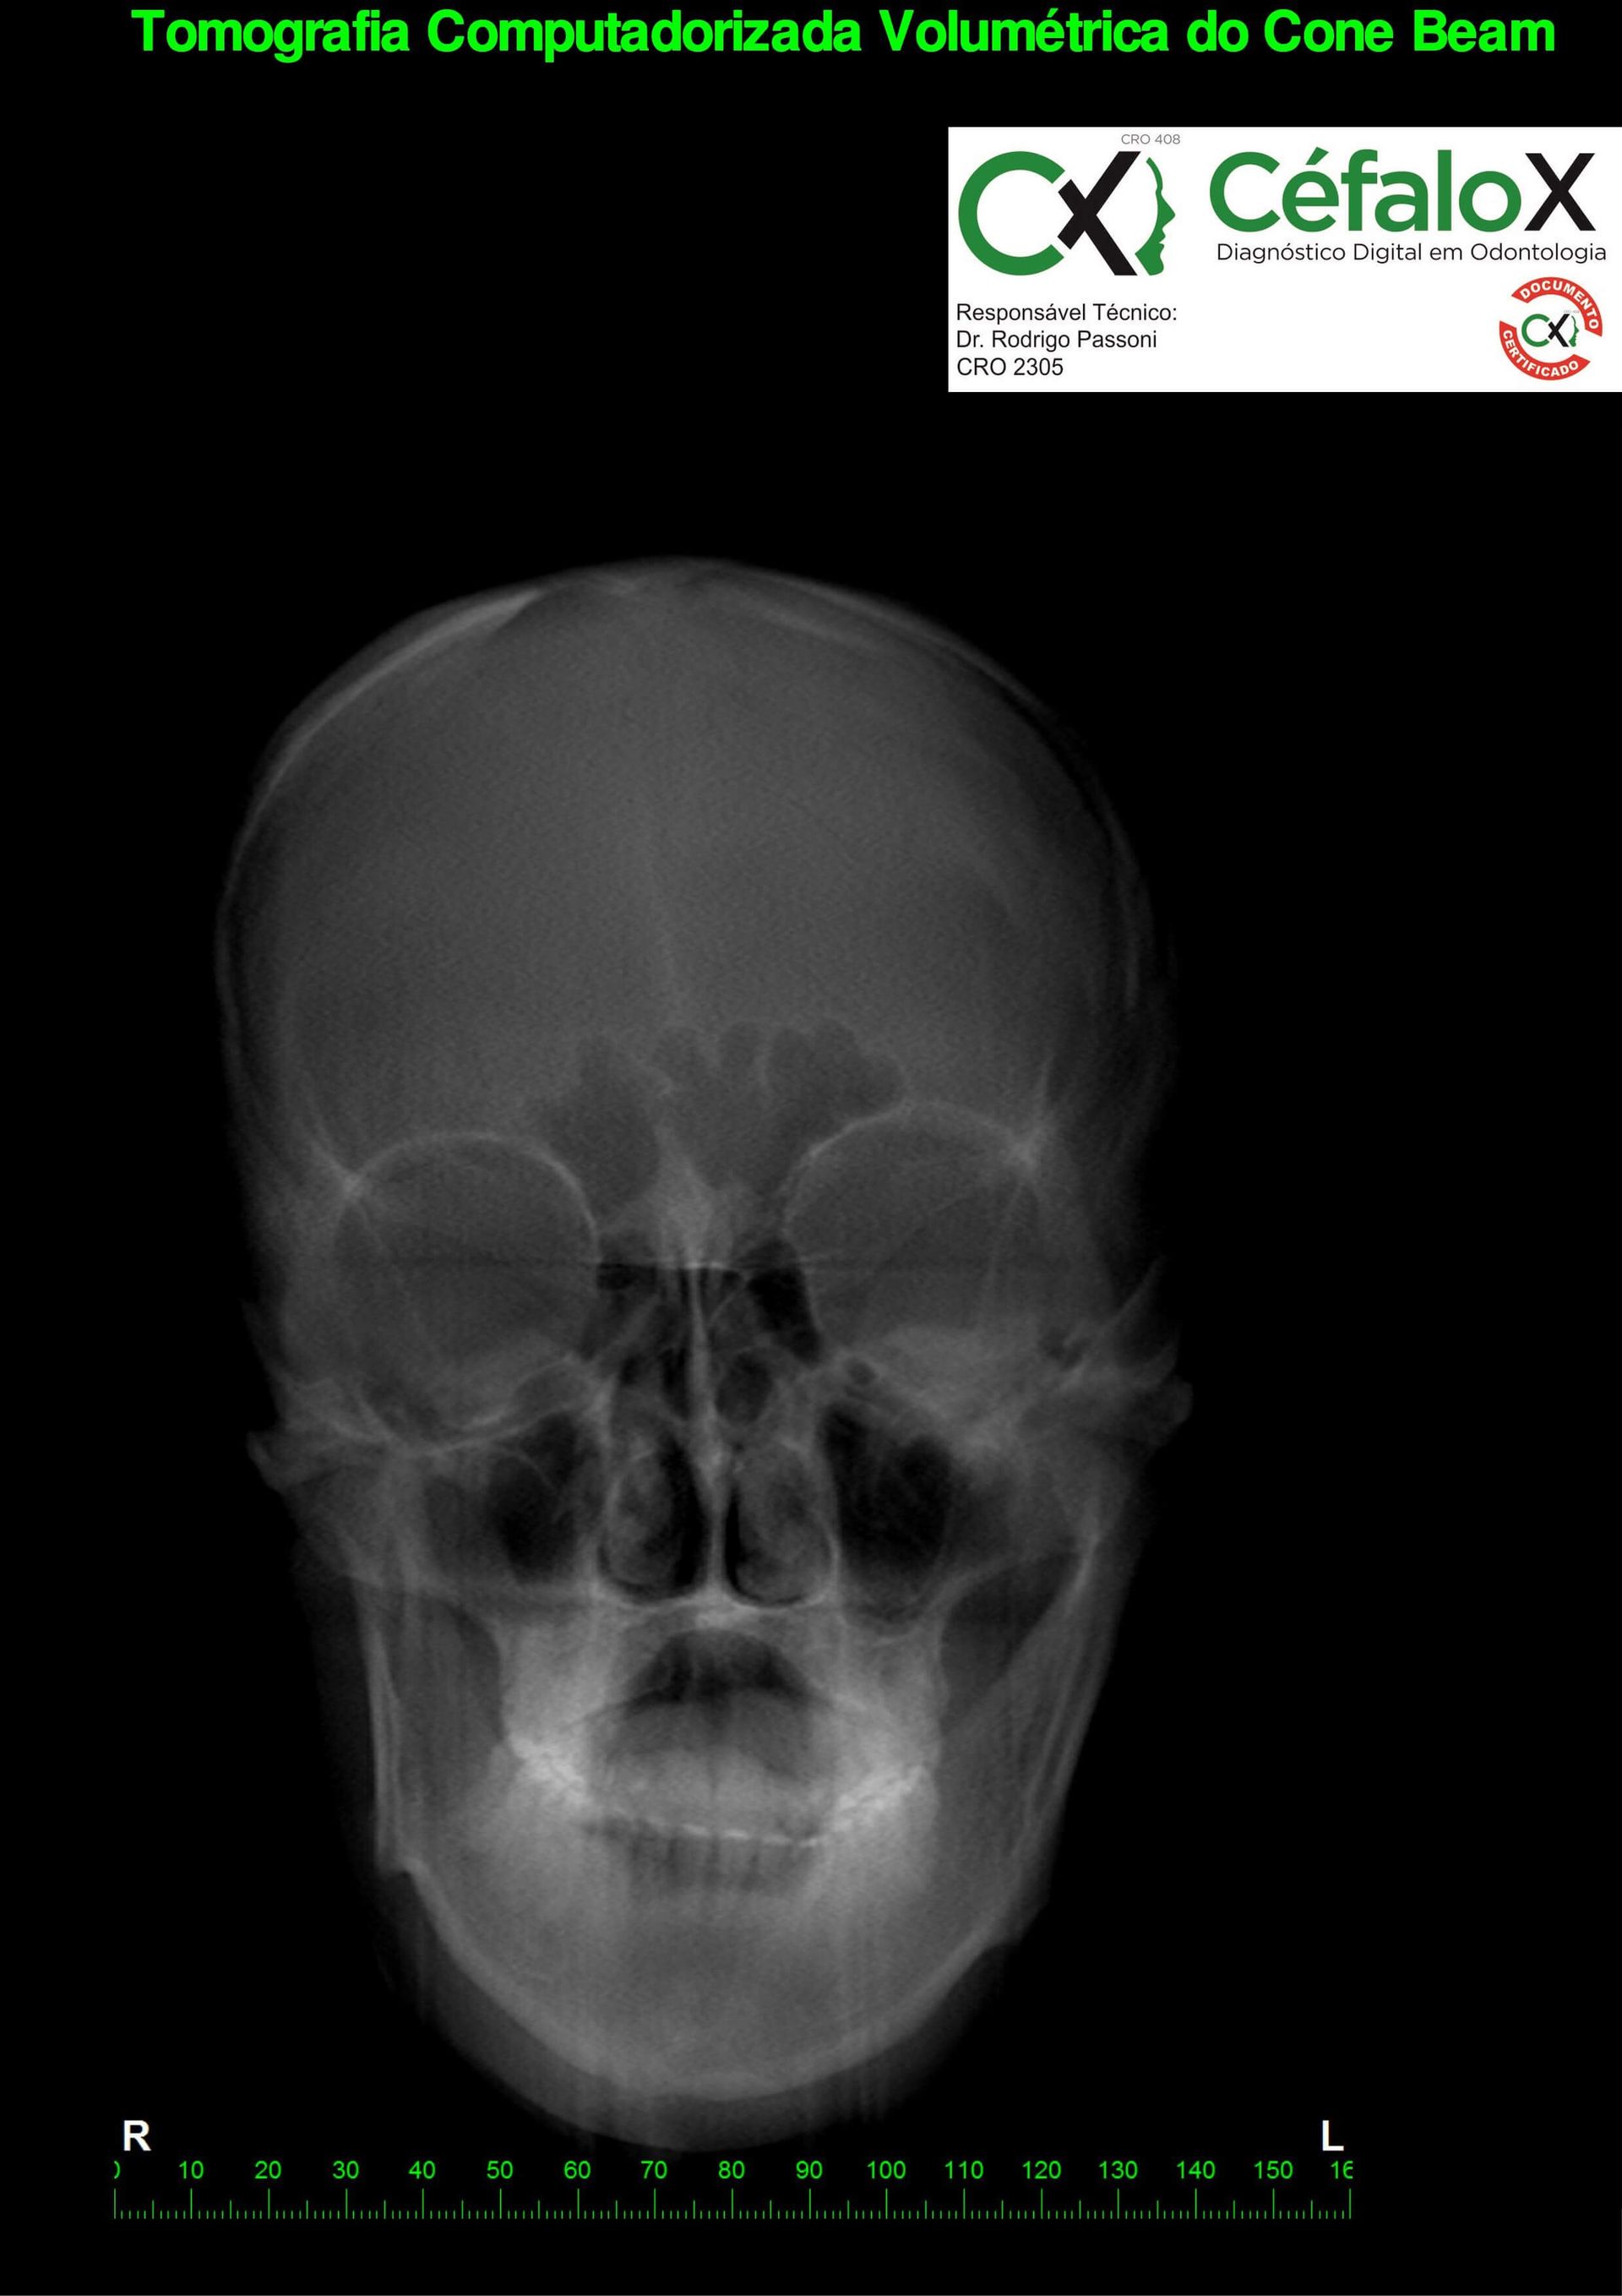

TC de face (do Hióide à Glabela), reconstrução 3D do tecido ósseo, radiografia panorâmica, telerradiografia lateral com traçado, cortes transversais e axial de maxila e mandíbula e arquivo DICOM- entregue em pasta de Pvc.

TC de face (do Hióide à Glabela), reconstrução 3D do tecido ósseo, radiografia panorâmica, telerradiografia lateral e frontal com traçado, cortes transversais e axial de maxila/mandíbula e arquivo DICOM – entregue em pasta de Pvc.

TC de face (do Hióide à Glabela), reconstruções 3D do tecido mole/ósseo/vias aéreas, radiografia panorâmica, telerradiografia lateral e frontal com traçado, cortes transversais e axial de maxila/mandíbula, ATM e arquivo DICOM – entregue em pasta e caixa de Pvc.